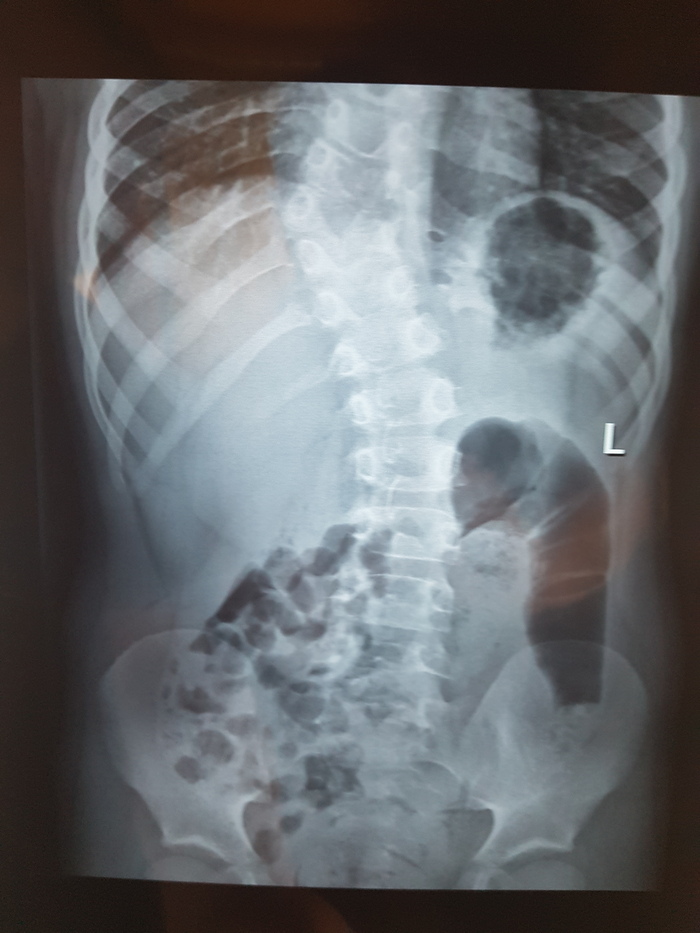

Нужна помощь вертебролога

Добрый день, сообщество! Нужна помощь, совет, консультация. Что угодно, что-бы мне понять что делать дальше. У ребенка при проведении рентгенографии в районой поликлинике выявили полупозвонок Th9.

В поликлинике хирург-ортопед настоятельно рекомендовал искать специалистов вертебрологов-ортопедов.  На пикабу встречаются совершенно разные специалисты, и может есть вертебрологи, ортопеды, которые смогут подсказать куда нам лучше обращаться. Насколько я понимаю, речь идет про операцию. Или возможны варианты? А если операция, то где ее могут сделать? И сколько примерно может стоить? И можно ли ее провести по ОМС или по квоте.

Вобщем, нуждаюсь в любой помощи, совете, консультации. Спасибо. Без рейтинга

Р.с. ребенку 7,5 лет. Территориально Москва